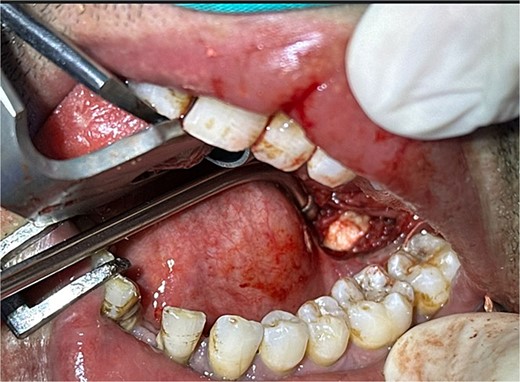

The accuracy of navigation was periodically verified by referencing stable bony landmarks, such as the mental foramen and mandibular condyles, with the navigation probe. Realignment was conducted as needed to ensure consistent anatomical mapping and precise localization of the submandibular stone (Fig. 2). After surface registration, a 1 cm mucosal incision was made intraorally at the nearest point indicated by the navigation pointer, parallel to the anticipated course of the Wharton duct. Blunt dissection was performed to expose the duct, with navigation toward the stone guided by the system. Great care was taken to protect the lingual nerve throughout the procedure. The depth of dissection was gradually advanced by periodically verifying the position with the navigation pointer probe (Fiagon) to maintain precision. During dissection, the stone was accurately located within the gland parenchyma using real-time visualization, and it became palpable, distinguished by its unique color and texture (Fig. 3). The stone was fragmented and removed in pieces because it was fixed (Fig. 4). The surgical field was flushed with saline to remove any residual stone debris, and the incision was closed with 4/0 Vicryl, which is an absorbable suture.

Intraoral extraction of the submandibular gland stone during the procedure.